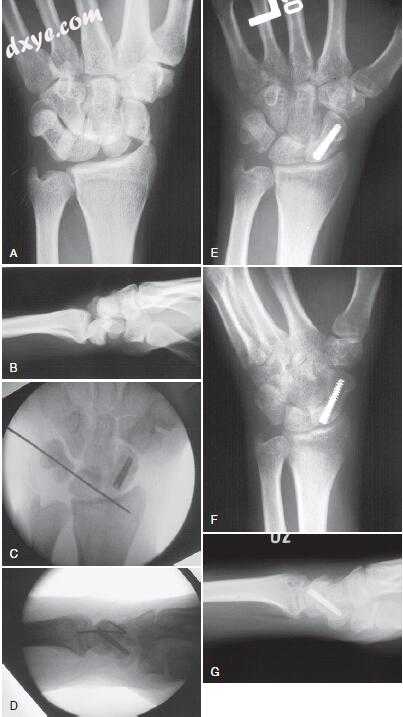

19.jpg

图.19  经舟骨月骨周围骨折 - 脱位。 手术前后位(PA)(A)和侧位(B)X线片。 手术中PA(C)和侧位(D)透视图像。 手术后3个月,手腕的PA(E),斜(F)和侧(G)X线片。